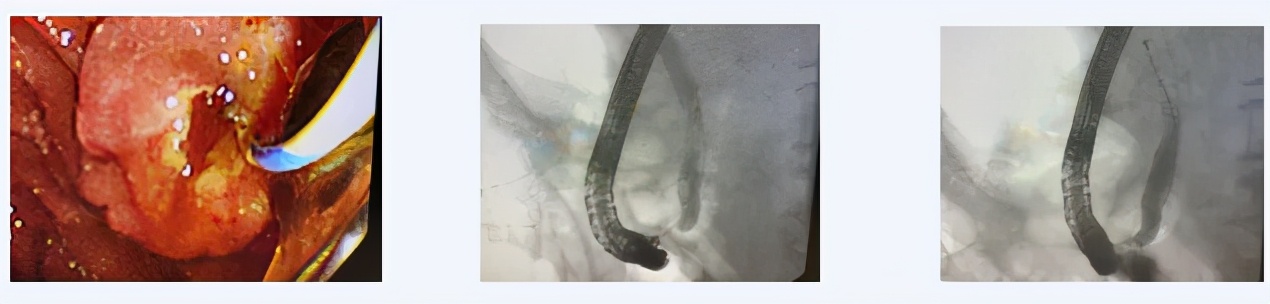

患者90岁,退役老红军,因“心力衰竭,休克状态”收入西青医院心内科,入院后进一步评估病情,确诊为“胆总管结石,急性胆管炎,感染性休克,心力衰竭”,普通外科主治医师王利军会诊后建议转外科病区治疗。该患者转入外科后,完善检查积极抗感染抗休克治疗评估患者病情,考虑患者相关症状均与胆系结石梗阻所致的感染密切相关,考虑到患者高龄,心衰IV级,休克状态,无法耐受手术,且患者危急重症,无法进行全麻治疗,经沟通建议首选局麻下ERCP微创治疗。随后在天津市南开医院内镜专家的指导下,与内镜室护理团队在介入室局麻下,通过十二指肠镜成功为该患者清除胆总管内多发结石放置BD管引流胆汁,解除梗阻后患者病情迅速稳定,恢复良并好出院。

经内镜逆行胰胆管造影(ERCP)是指将十二指肠镜插至十二指肠乳头,由内镜活检管道插入造影导管至胆管或胰管,经造影导管注射造影剂作X 线胰胆管造影。此操作主要适用于1、疑有胆总管结石、肿瘤、炎症或梗阻性黄疸原因不明者;2、胆囊切除术后或胆总管术后胆系症状复发;3、怀疑胰腺肿瘤、慢性胰腺炎或复发性胰腺炎缓解期;4、十二指肠乳头或壶腹部肿瘤;5、原因不明上腹痛,怀疑胆胰疾病;6、其他胆系疾病需行内镜下治疗者。

由于传统手术创伤大,风险高,恢复慢,对于年老、体弱,基础疾病较多,难以耐受麻醉及手术的患者均可通过局麻下行ERCP解决。因胰腺肿瘤或胆总管肿瘤引起的阻塞性黄疸严重患者,肝功能异常不能行手术治疗,均可行ERCP,通过行胆汁外引流或内引流达到解除梗阻,降低黄疸,提高患者生活质量,延长恶性胆道梗阻肿瘤患者的生存时间,具有并发症少、死亡率低、存活时间长、不损伤肝脏等优点。